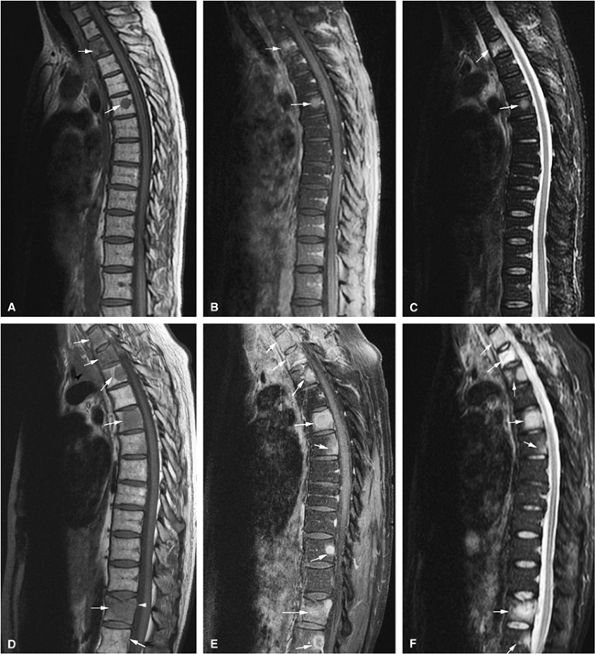

FIGURE 13.20 ● Extensive myelofibrosis following chemotherapy for leukemia. (A) The bone marrow exhibits diffuse marrow fibrosis, which is of low signal intensity on a sagittal T1-weighted image of the lumbar spine. Low-signal-intensity myelofibrotic marrow is seen on these coronal T1-weighted (B) and fat-suppressed T2-weighted (C) images of the knee. (D) Abnormal sclerosis of the spine, sternum, and ribs is seen on the axial CT image (arrows).